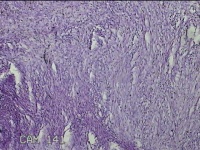

左大腿皮下结节

性别

女

年龄

30岁

临床诊断

皮下结节

一般病史

发现左大腿皮下结节1年余。

标本名称

大体所见

灰白粉红色组织1.7x0.8x0.3cm一个,表面带梭形皮肤 1.3x0.7cm,皮下见结节1.7x0.7cm一个,切开结节呈实性,切面灰白灰白粉红色,质中。

图2